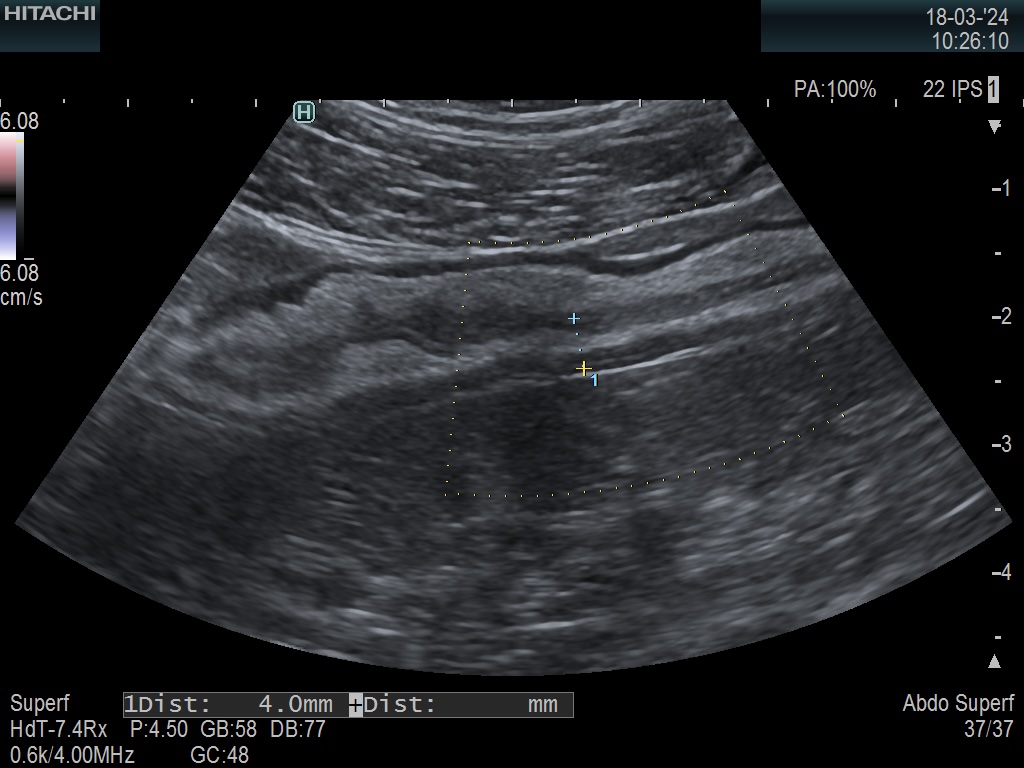

Paroi 4,1 mm et Doppler négatif (Limberg 0)

Score de Milan = 5,74 (1,4 x4,1 +0)

Donc la maladie va mieux, l'évolution est favorable

Mais la maladie reste active (non cicatrisée).

Colon transverse non épaissi